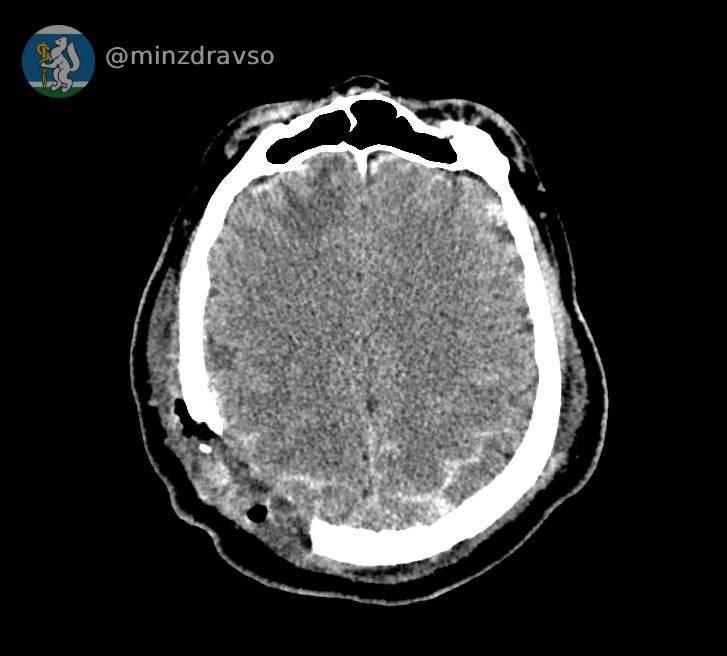

Мужчине сделали компьютерную томографию, чтобы увидеть его травмы и понять, где находятся повредившие мозг костные отломки. Самый острый из них мог в любую минуту привести к смерти, сообщили в Департаменте информационной политики Свердловской области.

- удалили отломки костей и гематомы;

- восстановили целостность твёрдой мозговой оболочки.